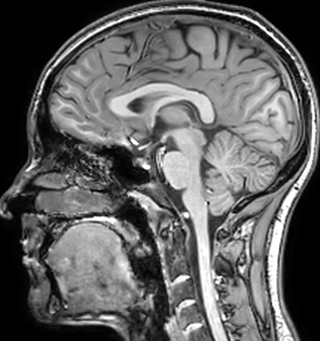

T1 - weighted

Myelin water imaging (echo 1)

T1 - Weighted, Myelin Water Fraction Superimposed

Spinal cord coverage

Smaller, more isotropic voxels

Excellent detail in quantitative maps

Images courtesy of Adam Dvorak, Department of Physics and Astronomy, University of British Columbia